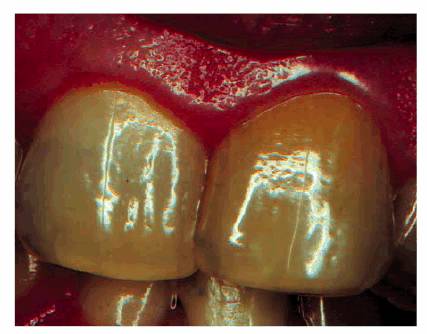

certain root canal sealers and filling materials (Figures 19-6A 19-6B, and 19-6C). A yellow or brown (Figures 19-7A, and 19-7B) unrestored crown often represents

Figure 19-7A: The crown of this maxillary central incisor discolored gradually over a 3-year period following a concussion injury. The complete fill-in of the pulp chamber with dentin is the cause of the yellowish brown hue. In the absence of periapical radiographic changes and clinical symptoms, endodontic therapy is not indicated.

Figure 19-7B: Radiograph of a similar maxillary central incisor 10 years after a concussion injury. The pulp chamber is filled in with dentin producing the discoloration. In this case, there was pulp death years after the discoloration appeared. Because the pulp canal was obliterated, a surgical approach was used to seal the apex.